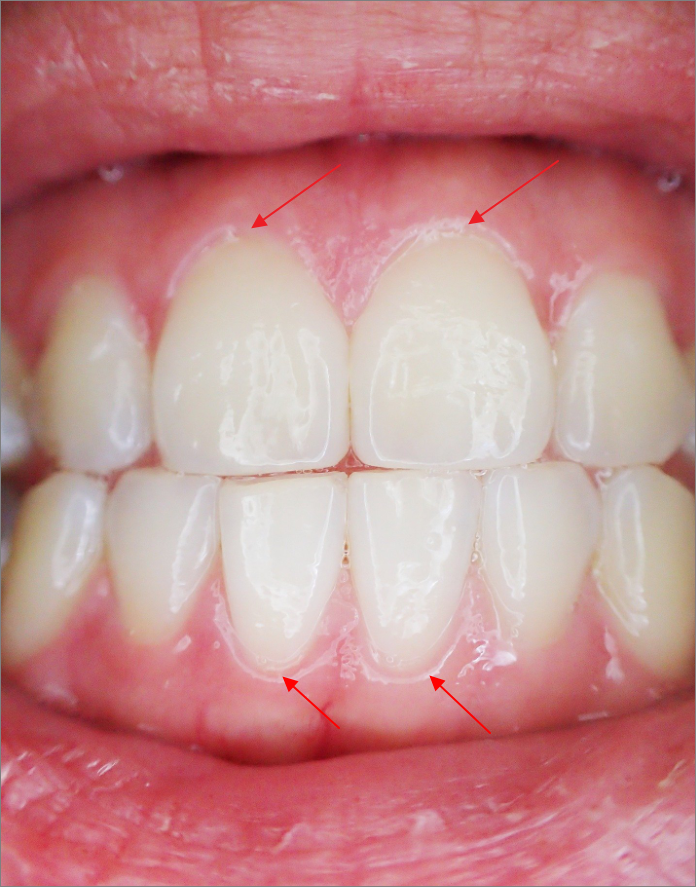

잇몸과 치아가 만나는 (사진에 화살표로 표시한) 부분을 치경부라고 함.

이곳이 마모되는 것이 치경부 마모증.

치경부가 마모되면(=얇아지면) 치아의 신경과 가까워지면서 쉽게 이가 시리게 됨.

치아의 모양으로 봐도 치경부가 신경과의 거리가 가장 가까움.